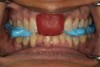

Fig 1. Preoperative frontal smile view.

Figure 1

A 40-year-old female patient complained of short teeth and asked for various options to improve her smile. On clinical examination, the palatal surfaces of the maxillary anterior teeth were found to be eroded, with the residual tooth structure having a smooth and shiny appearance (Figure 1 through Figure 3). In MIP, no restorative space was available, as the lower anterior teeth fit tightly into the upper palatal surfaces, making this a clinically challenging situation to treat conservatively. In most cases of conventional treatment protocols, such upper teeth are devitalized and restored with crowns that structurally leave the teeth in a compromised condition.10